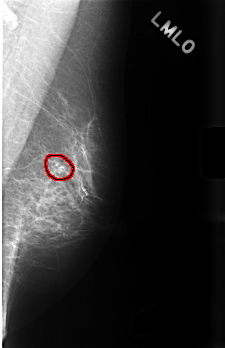

C_0476_1.LEFT_MLO

LEFT_MLO LINES 4520 PIXELS_PER_LINE 2920 BITS_PER_PIXEL 12 RESOLUTION 50 OVERLAY

FILE: C_0476_1.LEFT_MLO.OVERLAY

TOTAL_ABNORMALITIES 1

ABNORMALITY 1

LESION_TYPE CALCIFICATION TYPE PLEOMORPHIC DISTRIBUTION CLUSTERED

ASSESSMENT 4

SUBTLETY 5

PATHOLOGY BENIGN

TOTAL_OUTLINES 1

BOUNDARY